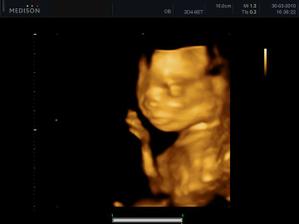

30.03. - (20+5), tak na dnešní kontrole dopadlo všechno na 1*, vážíme už 380g a z našeho Marečka se nakonec vyklubala Amálka, která měla mezi nožičkama zamotenej pupečník 😀 Pan doktor říkal, že tentokrát, je to opravdu na 100%

27.04. - (24+5) video, tak z videa nakonec sešlo. Dohodli jsme se s panem doktorem, že se mu ozvu, tak za 14 dní, až Karolínka ještě povyroste. Teď má v bříšku ještě moc místa a nebylo by to úplně ono. Tak jsme alespoň dostali několik foteček a dva doktoři nám potvrdili, že jde skutečně o holčičku.

video se povedlo, máme asi 6 cca 5 - 10ti vteřinových videíí.Bylo to super. Karolínka se zase mlela jako drak. Je taková živoučká 😀